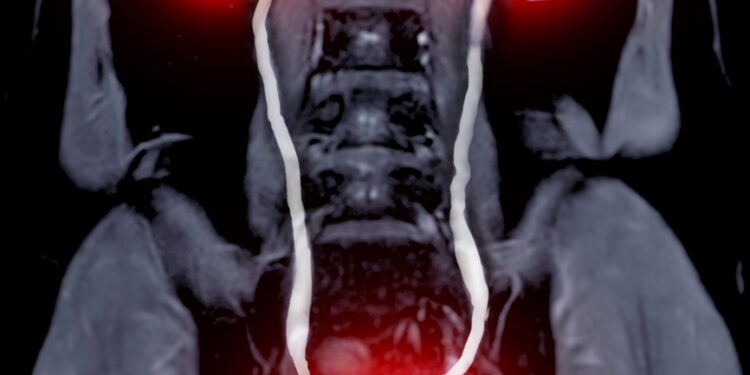

- Kompiuterinė tomografija (KT) – detali vidaus organų nuotrauka sluoksniais, dažnai atliekama su kontrastine medžiaga, tačiau esant inkstų pažeidimui kontrasto gali būti vengiama.

- Magnetinio rezonanso tomografija (MRT) sukuria tikslias minkštųjų audinių vidaus nuotraukas pasitelkiant magnetinį lauką ir radijo bangas.